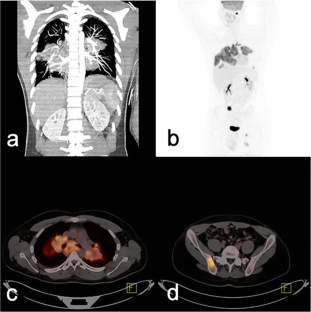

Fig. 3